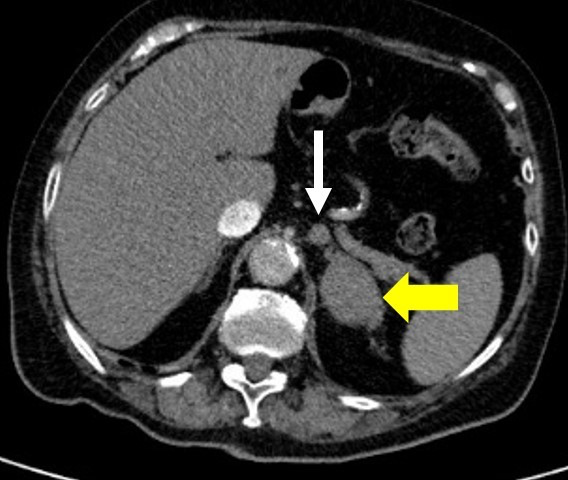

- Adrenal: CT/MRT Abdomen

| Maligne | Adrenokortikales Karzinom, Metastasen (z. B. Lunge, Mamma, Niere, Melanom) | Oft große Tumoren, Wachstum, evtl. hormonaktiv | > 4–6 cm oder suspekt → Adrenalektomie |

CT/MRT: Adenom < 10 HU (fettreich), Karzinom > 20 HU, suspekt bei schnellem Wachstum